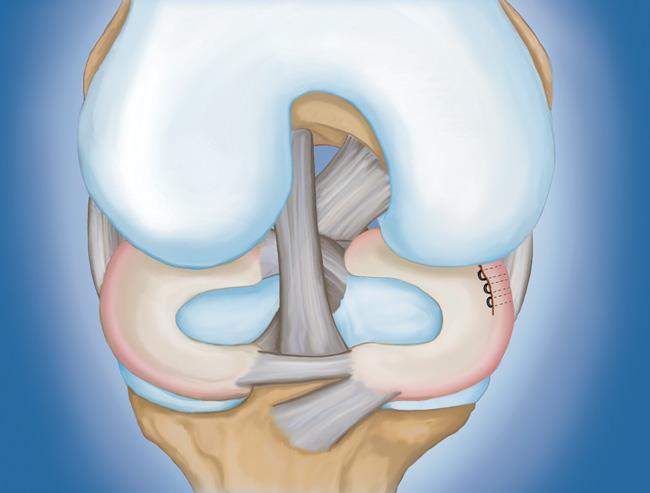

- 半月板修復(fù)。 一些半月板撕裂可以通過將撕裂的碎片縫合(縫合)在一起來修復(fù)。撕裂能否成功修復(fù)取決于撕裂的類型,以及受傷半月板的整體狀況。因?yàn)榘朐掳灞仨氁黄鹩希迯?fù)的恢復(fù)時(shí)間比半月板切除術(shù)長。

初步愈合完成后,您的醫(yī)生將進(jìn)行康復(fù)鍛煉。定期鍛煉以恢復(fù)膝關(guān)節(jié)的靈活性和力量是必要的。您將從鍛煉開始,以改善您的運(yùn)動范圍。力量訓(xùn)練將逐漸添加到您的康復(fù)計(jì)劃中。

在許多情況下,康復(fù)可以在家中進(jìn)行,但您的醫(yī)生可能會建議您與物理治療師一起工作。半月板修復(fù)的康復(fù)時(shí)間約為3至6個(gè)月。半月板切除術(shù)需要更少的愈合時(shí)間——大約3到6周。